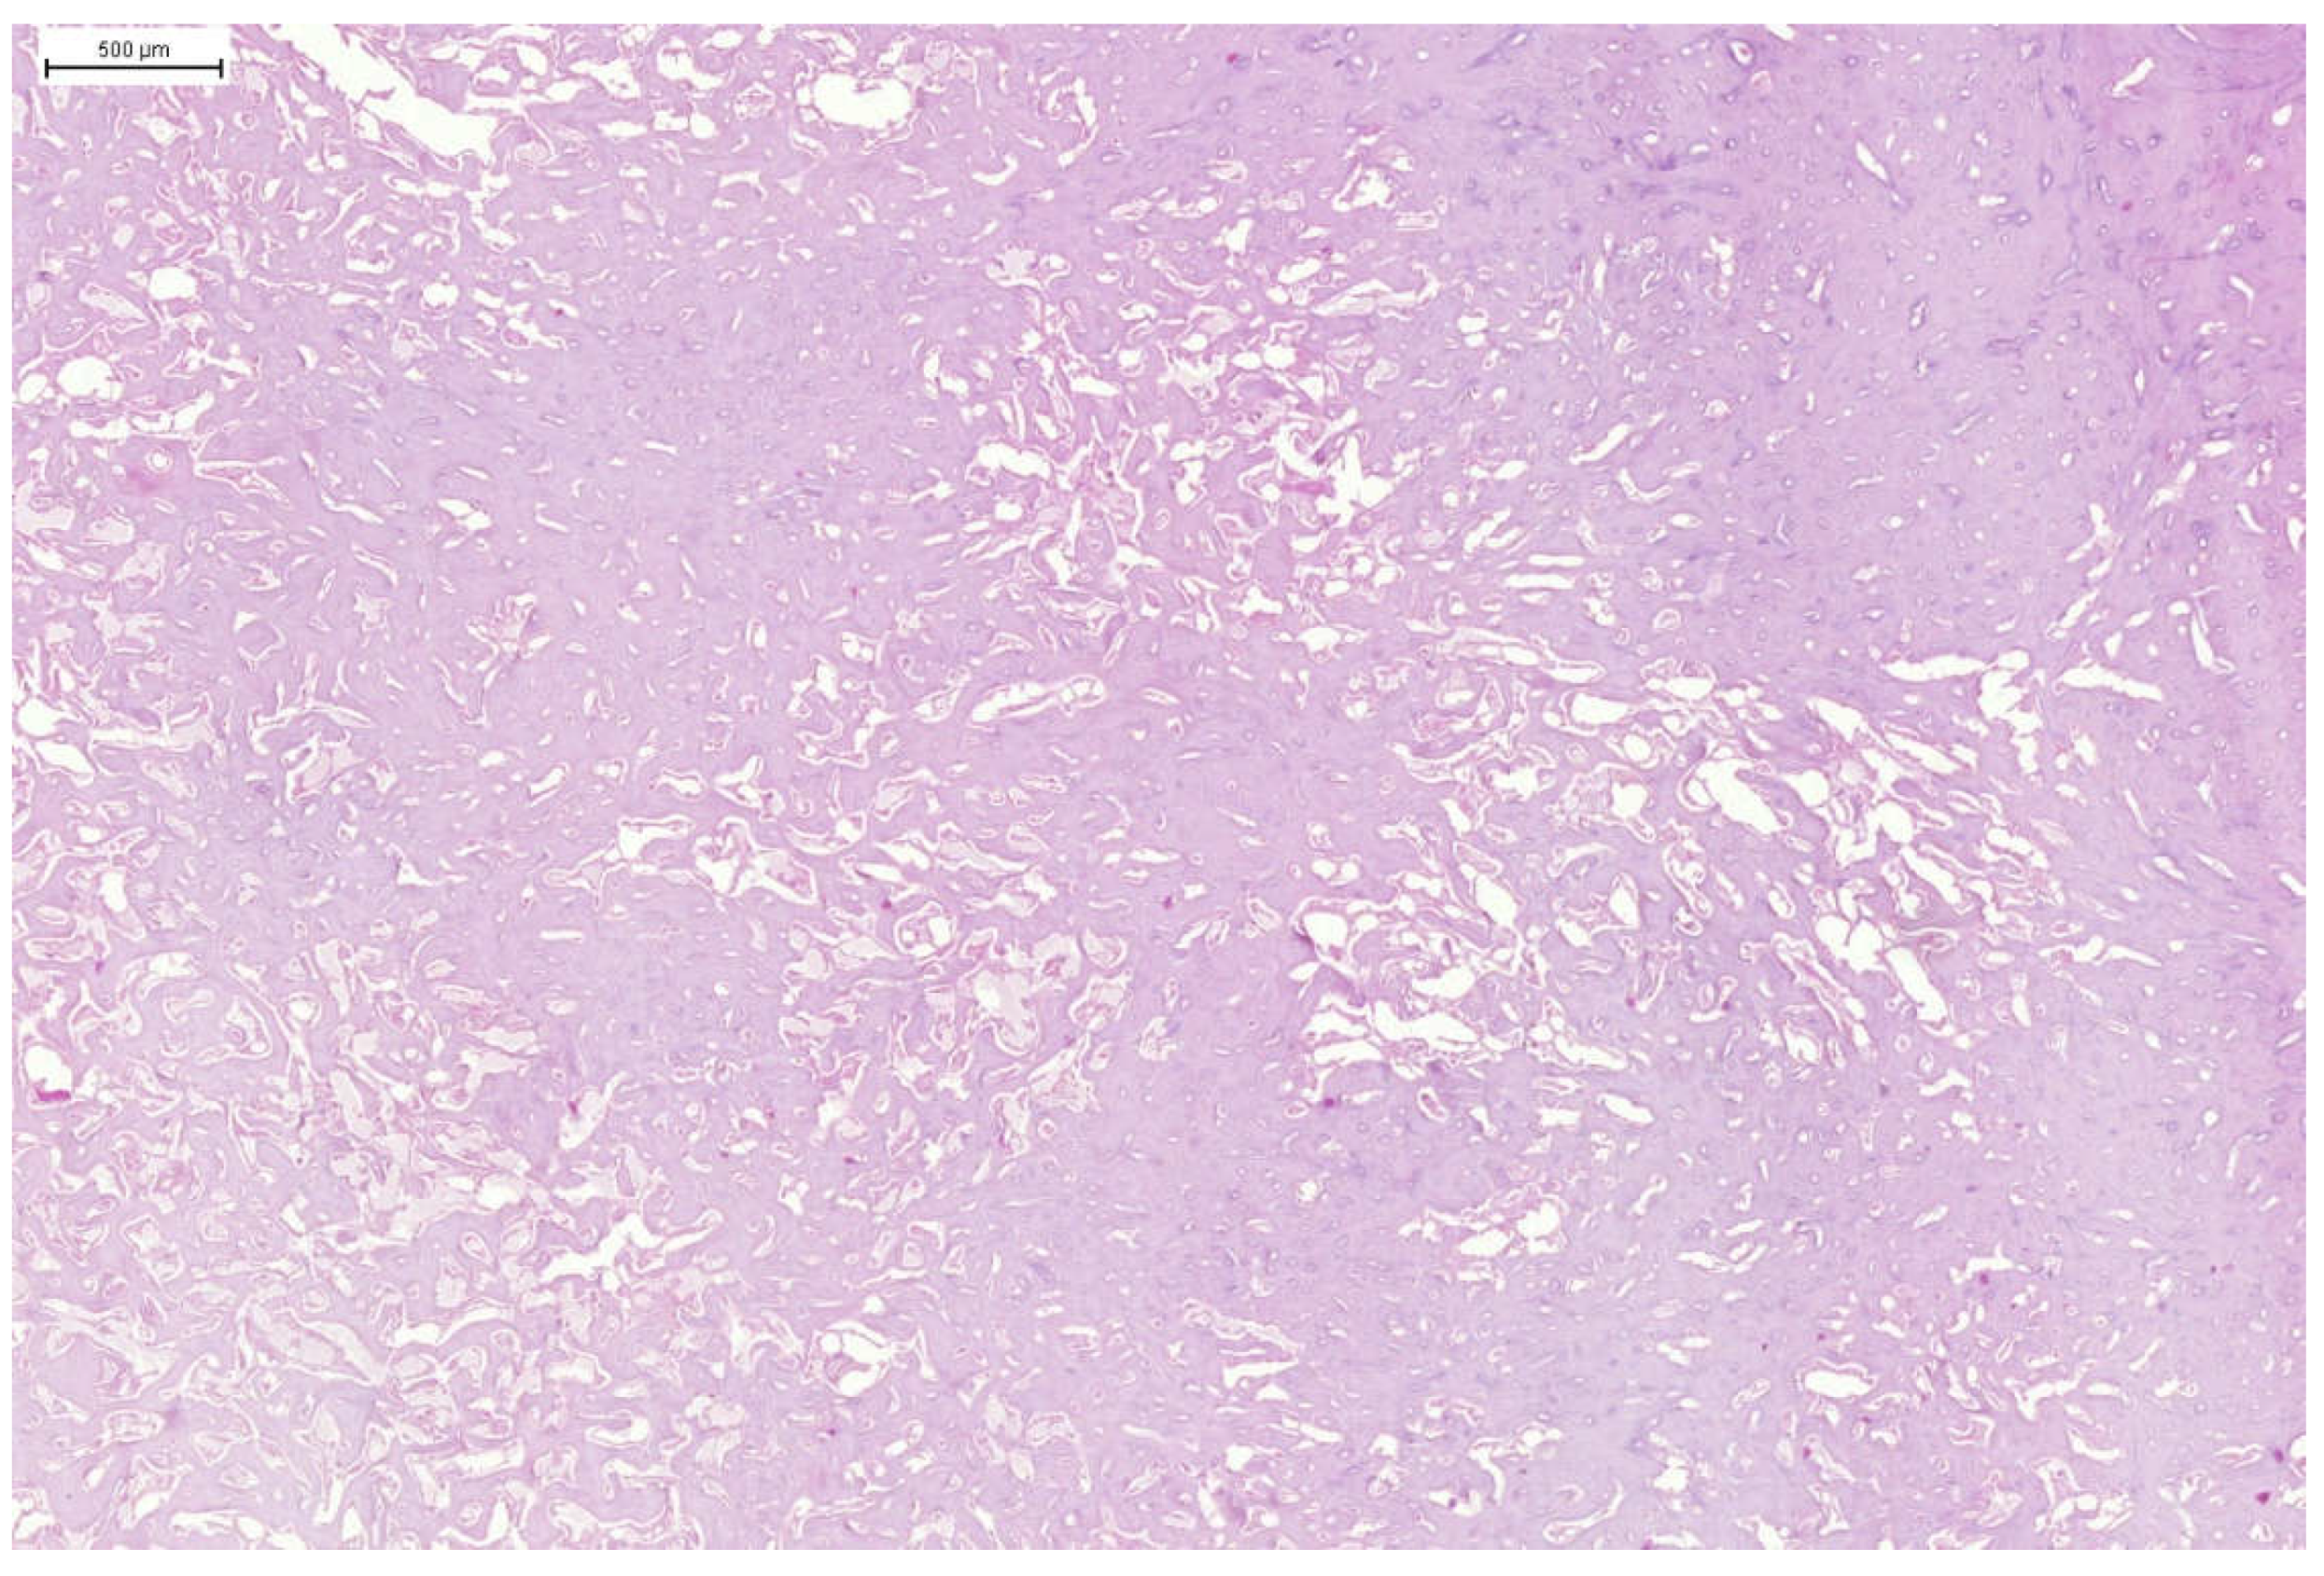

Histopathological examination confirmed the presence of a well-defined benign neoplasm derived from bone tissue arose from the body of the cervical vertebrae (Figure 6). The tumour was well circumscribed and consisted large area of irregular, disorganized bone trabeculae, usually surrounded by a layer of neoplastic osteoblasts (Figure 7 and Figure 8). Between the trabeculae well-vascularised connective tissue was observed, suggesting intense metabolic activity within the cancer. Histopathological examination of the tumour showed that the change was mild and derived from bone tissue. The tumour has been classified as an osteoma. The microscopic evaluation of the organs and tissues did not reveal any pathological changes or metastasis.

Figure 7. Domestic goose. Tumour mass. Large dense area of trabecular bone with visible irregular holes containing blood vessels and neoplastic osteoblasts. HE staining.

Figure 8. Domestic goose. Tumour mass. Large area of trabecular bone with visible irregular holes containing blood vessels and osteoblasts. HE staining.